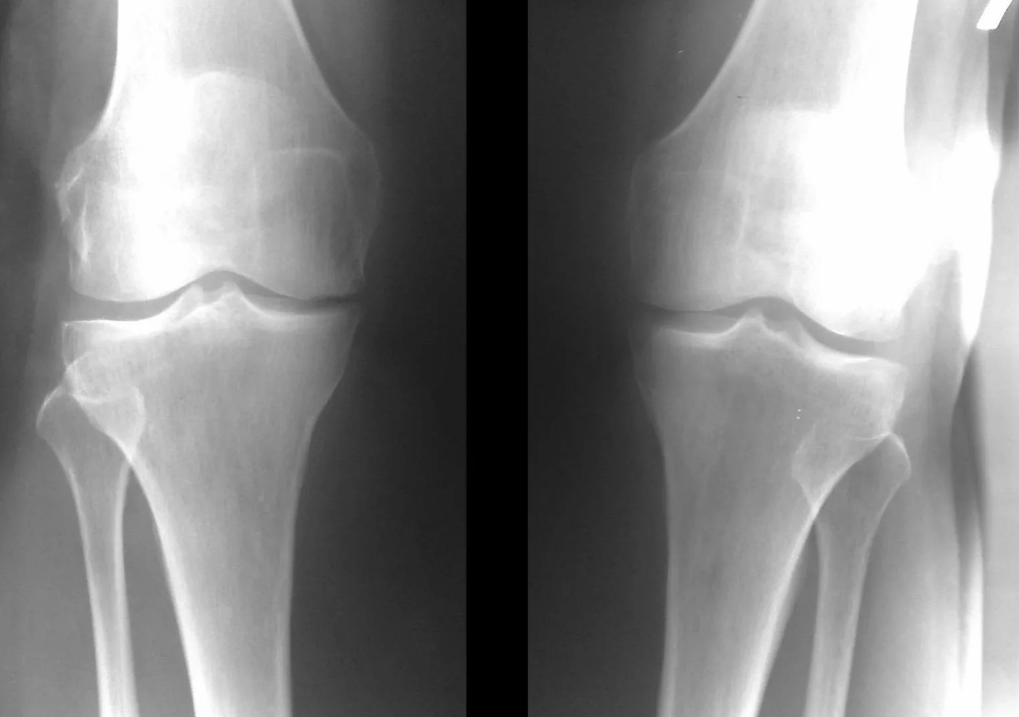

Kelio sąnario artrozės instrumentinė diagnostika

Daugeliu atvejų pakanka kelio sąnario apžiūros ir rentgeno nuotraukos dviejose projekcijose (tiesioginėje ir šoninėje). Klinikiniai duomenys ir vaizdai padeda nustatyti ligos stadiją.

Ankstyvosiose ligos stadijose, esant nedideliems kaulinio audinio pakitimams, rentgeno tyrimas nėra toks vertingas. Šiame etape gonartrozę galima diagnozuoti atliekant artroskopiją. Metodo tikslumas yra labai didelis; tik jos invazinis pobūdis ir kaina gali jį sustabdyti.

Ultragarsas neleidžia aiškiai vizualizuoti sąnario kremzlės ir intraartikulinių struktūrų pokyčių. Naudojant MRT, 85% tikslumu galima nustatyti sąnario kaulo, kremzlės ir minkštųjų audinių struktūrų bei subchondrinio kaulo pokyčius. Scintigrafija gali būti naudojama periartikulinio kaulinio audinio metaboliniam aktyvumui įvertinti.